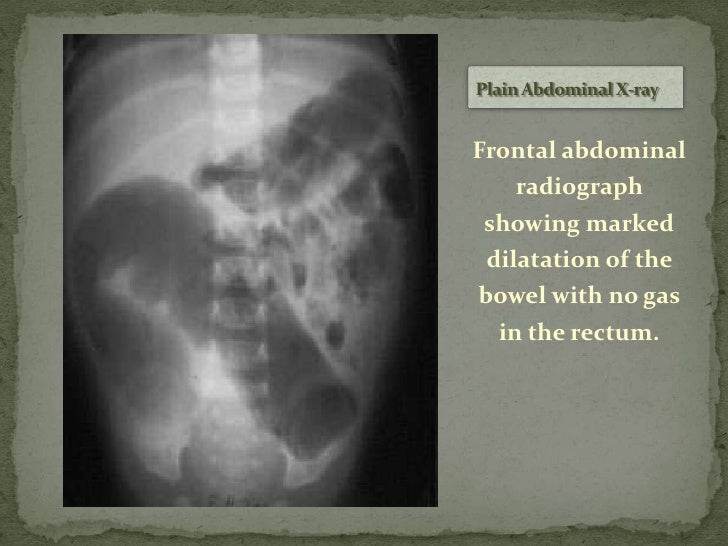

This is the most valuable radiologic study for establishing the diagnosis. Abdominal plain X-ray findings associated with Hirschsprungs disease may include. Radiography performed in children with Hirschsprungs disease yields findings similar to those in other forms of distal small intestine obstruction including variable gaseous distention of the colon and small bowel often with air-fluid levels.

An X-ray of the abdomen will show a narrowed colon obstruction and dilated exceptionally enlarged intestine above the obstruction. Congenital megacolon or megarectum.